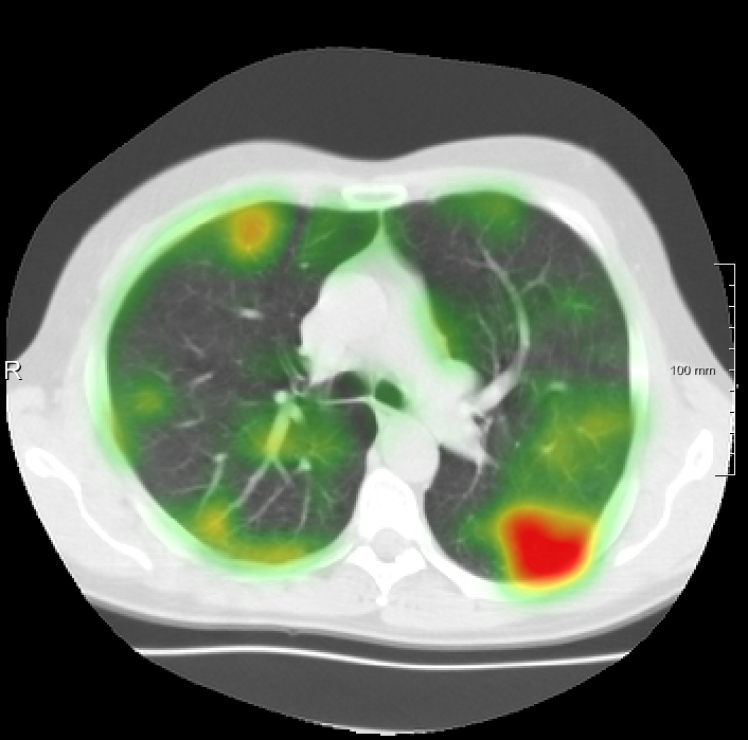

In total we generate 14 basis types of artificial DVFs: 5 single frequency, 4 mixed frequency, 4 respiratory motion and 1 identity. The precise settings of the parameters are available in Table I and examples are given in Fig. 4. The histograms of the Jacobians are also available in this figure. When the spatial frequency is increased, the Jacobian histograms will spread more, which shows that local relative volume changes are increased. The value of , the maximum artificial displacement along each axis, is chosen as 20, 15 and 7 for RegNet4, RegNet2 and RegNet1, respectively.

For the DIR-Lab-4DCT database, a comparison between RegNet and affine, B-spline (three resolutions), an advanced conventional registration method using sliding motion (Berendsen et al., 2014) and three other CNN-based methods (Eppenhof and Pluim, 2018; de Vos et al., 2019; Sentker et al., 2018) is available in Table IV. It can be seen that training with “S+M” improved performance slightly with respect to just “S”. Adding the respiratory motion category improved performance substantially, as these are inhale-exhale pairs; this is predominantly caused by the patients where the TRE after affine registration was still quite large. An example visualization is also available in Fig. 5(f), showing that adding the respiratory motion category can align images better in the diaphragm region. The advanced conventional registration method that leverages sliding motion (Berendsen et al., 2014) is still better than RegNet. Note that RegNet was not trained on the DIR-Lab-4DCT data, similar to Eppenhof and Pluim (2018); Sentker et al. (2018). However, de Vos et al. (2019) and Eppenhof and Pluim (2018)-DIR methods were trained on the same database but using cross-validation to report the results. Also note that the results reported in Sentker et al. (2018) are averaged over all phases of DIR-Lab-4DCT (T00 to T10), while the results of other CNN methods (including RegNet) are reported between the maximum inhale and maximum exhale phase (T00 and T50). These reported results are therefore likely somewhat better than the results for T00 and T50 only.